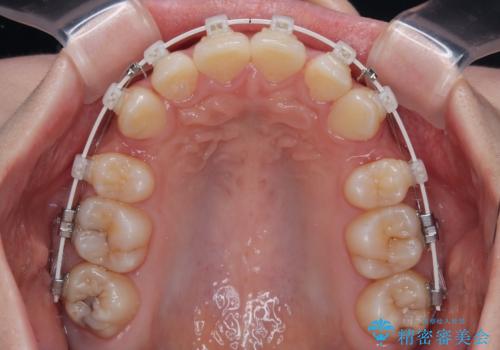

- 矯正装置

- 審美装置

- 上顎前歯の突出感を気にして来院された患者様です。

上下左右第一小臼歯4本を抜歯して、積極的に口元を引っ込めるよう、ワイヤー装置にて矯正治療を行うこととしました。